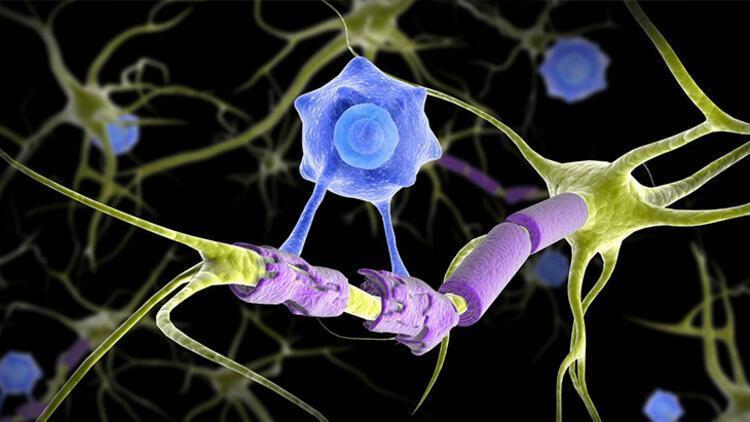

MS, vücudun bağışıklık sistemindeki normal işleyişi bozar. Bilindiği gibi normal şartlarda bağışıklık sistemi bizi hastalıklara karşı korur. Değişik nedenlerle bazen bu sistem vücuttaki normal dokuları da yabancı görmeye başlar ve onlara hücum eder.

Hastalık sinir sisteminin farklı bölgelerini farklı zamanlarda etkileyebilir. İlerleyen hastalık kişinin görme, yürüme, konuşma gibi yaşamsal öneme sahip fonksiyonlarını bozar.